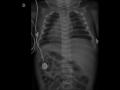

Figura 3 - Radiografia de tórax e abdome AP evidenciando cateter umbilical venoso bem locado, com extremidade visível sobre o corpo vertebral de T8 (seta).

Figura 4- Radiografia de tórax e abdome P evidenciando a trajetória do cateter umbilical venoso, passando pelo fígado, com extremidade locada na VCI ( seta).

Cateter umbilical venoso mal locado, com extremidade no átrio esquerdo (Figuras 1 e 2) com reposicionamento adequado (Figuras 3 e 4).

Na radiografia frontal de tórax e abdome, o cateter umbilical venoso apresenta uma trajetória retilínea,devendo sua extremidade estar situada à direita dos corpos vertebrais de T8 e T9, quando situado na veia cava inferior( Figura 3).

Na radiografia em perfil, após sua introdução pelo coto umbilical, o cateter inicialmente apresenta uma localização anterior, cursando a seguir para a parte posterior do abomen em direção ao fígado, sendo visibilizado no nível dos corpos vertebrais de T8 a T9, quando locado na veia cava inferior( figura 4).